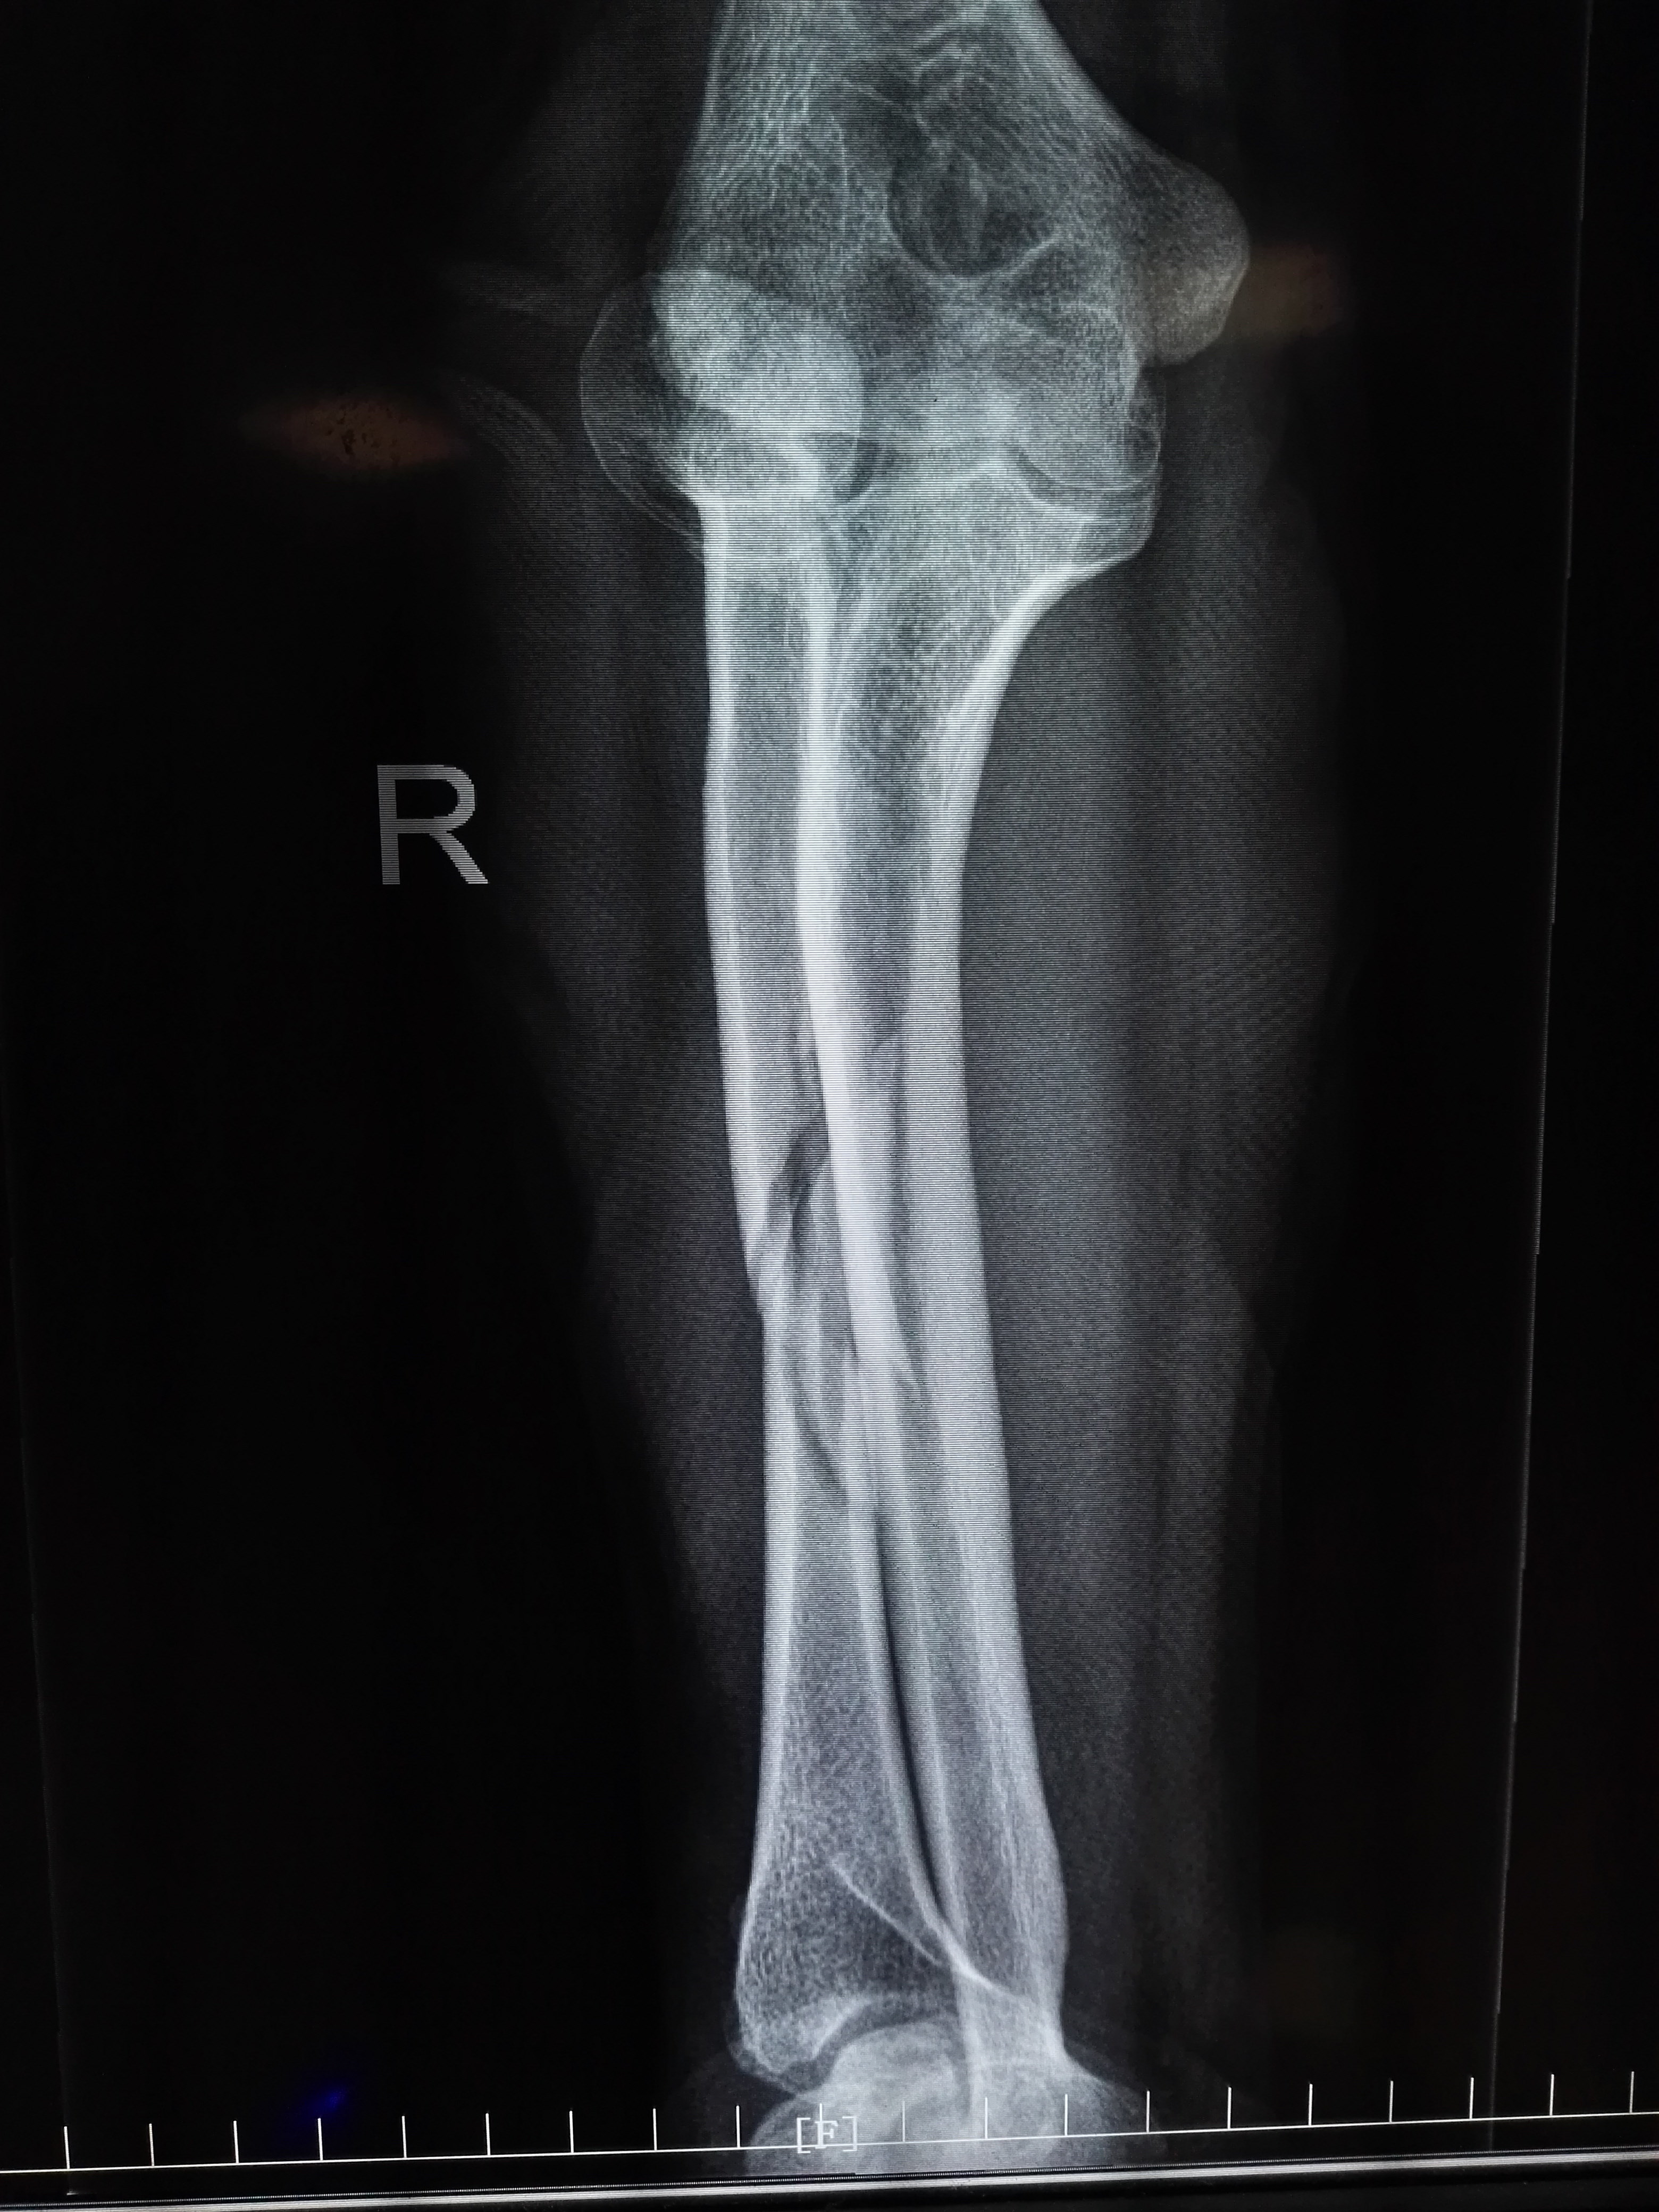

右侧尺骨骨折